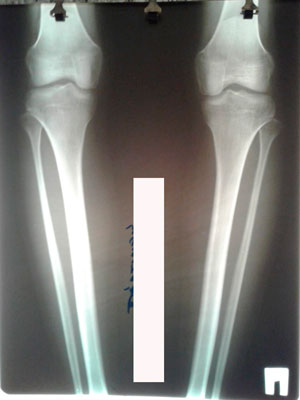

Исходник - 22 года.

Дата операции - 04.08.2020

image-04-08-20-09-38-4.jpg

image-04-08-20-09-38.jpg